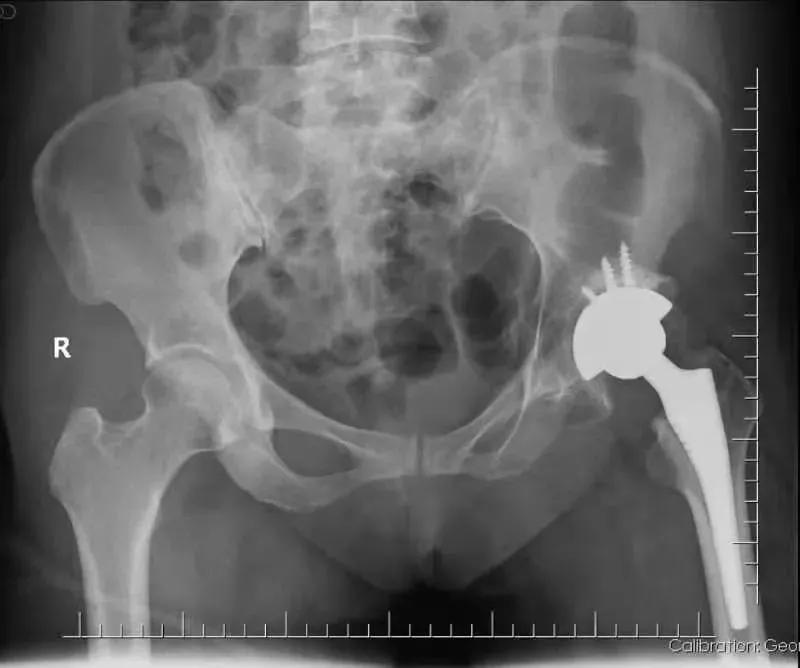

“间歇性疼痛,吃了很多止痛药,就没那么痛,没过多久又疼了,实在太难受了。”面对日益恶化的病情,张女士心急如焚。于是,张女士来到 佛山市第二人民医院骨一科 进一步诊治,通过骨盆X光片显示, 张女士左侧股骨头缺血性坏死 。

骨一科刘学东主任、黄思聪副主任医师组成手术团队共同为张女士完成了左侧全髋关节置换术、髋关节滑膜切除和髋关节松解术。

髋关节是人体最大的承重关节,对于人的站立、行走、蹲坐等日常活动都非常重要。髋关节置换术被誉为现代关节外科最成功的手术之一,为广大患者提供了最佳的治疗方法。